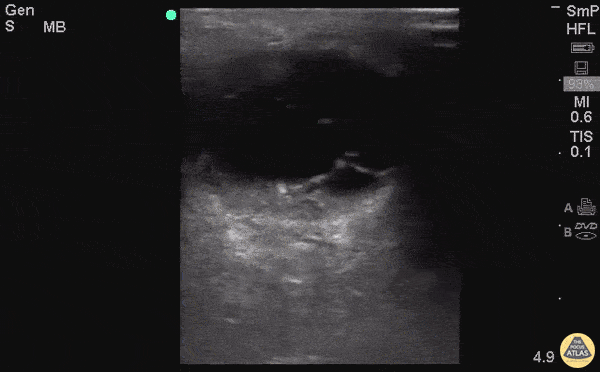

Renal/GU - Pyocele

83 y/o M with R testicular swelling, tenderness, concern for epididymitis vs orchitis. POCUS with septated fluid collection concerning for pyocele. Pycoeles are a urologic emergency that can lead to Fournier's and often require orchiectomy. Dr. Tess Sexton - Kings County/SUNY Downstate EM